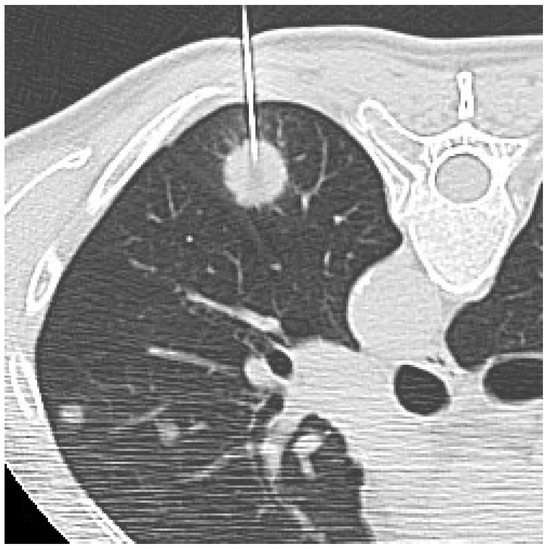

After local anesthesia of the skin and subcutaneous tissues with 10–20 mL of carbocaine, the initial puncture was performed without penetrating the pleura. CT images were obtained to check the position of the needle tip. At this point, if the direction was appropriate, the needle was pushed forward to the lesion according to the planned trajectory route, otherwise, insertion angle or position was corrected. When the nodule was penetrated, the needle tip was again checked on CT (Figure 1). After CT confirmation of a satisfactory needle tip position, biopsy samples for both histological and cytological analysis were collected.

Figure 1. CT-guided biopsy of a solid pulmonary lesion in the left lower lobe. Supine unenhanced CT scan obtained before sampling shows a satisfactory position of the needle tip within the lesion.